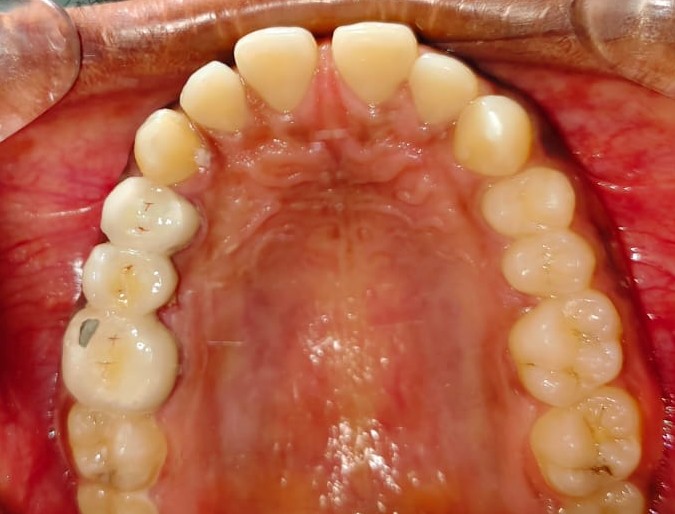

Sairam dental care located in Dharmapuri, with Leading Dentist In Oddapatti, is the Dental Hospital with exclusive root canal, Braces & Invisalign center. Led by renowned Drs Raghuraaman ( Periodontist) and Nivetha Raghuraaman ( Orthodontist) Sairam dental care offers gum treatment with expertise in laser, root canal treatment and digital smile correction with advanced technology aim to focus on aesthetics, comfort and precision. The clinic also specializes in Invisalign treatment, digital smile makeover, laser gum care, dental implants, root canal therapy, extractions and full-mouth rehabilitation blending compassionate care and clinical excellence.

Our professional, experienced, and passionate dentists make us the best choice for Invisalign treatment in Dharmapuri, providing top-notch dental services.